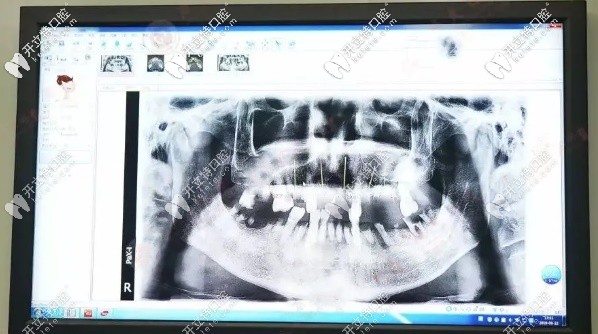

爺爺歲數(shù)大了,牙齒隨著年齡增長也在松動(dòng)脫落再加上之前也沒有重視過刷牙的問題,也從來沒注意口腔健康。造成現(xiàn)在能用的牙齒幾乎沒有,連吃飯都成了問題,更別說吃肉了,長此以往,營養(yǎng)跟不上,心情也不好了,那段時(shí)間見到爺爺都瘦了好多,這樣下去情況很糟。牙齒拍的片子